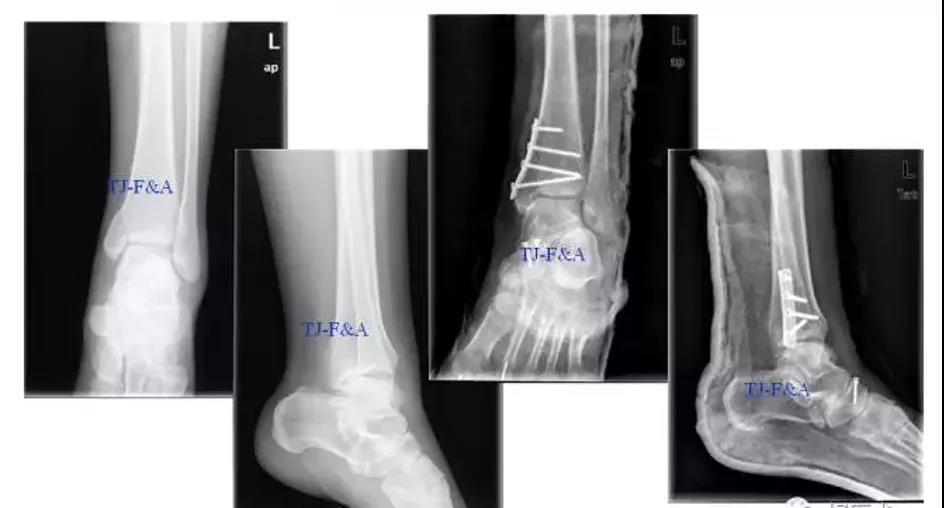

术前

术后DR

术前DR